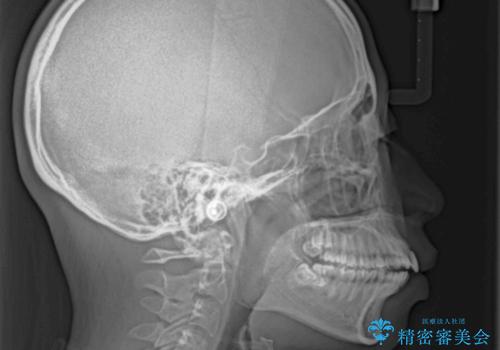

口が閉じられない 抜歯矯正で横顔の印象が劇的に変化

- 出っ歯と口の閉じにくさ、デコボコを気にして来院された患者様です。

口元の突出感を改善するため、上下左右第一小臼歯4本の抜歯を行い、ワイヤー装置による矯正治療を行うこととしました。

舌の突出癖により上下前歯は非接触であり、非常に前方に飛び出している状態でした。

舌のトレーニングをしっかりと行っていただき、口の閉じやすい歯並びに仕上げることができました。